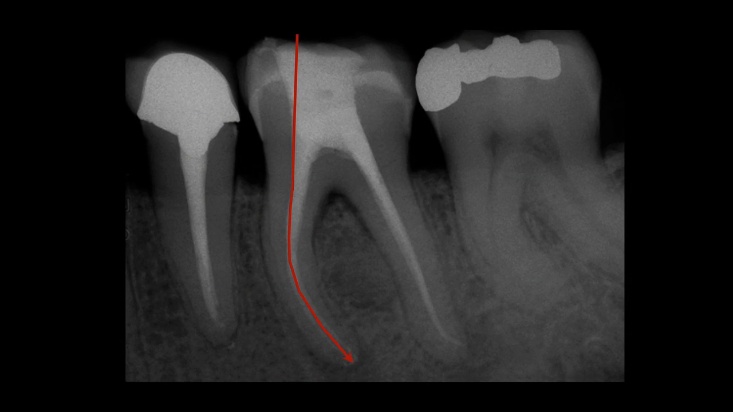

Криви канали

Сл. 20.24 Оперативен редослед на соодветно отстранување на коронарните пречки и спроведување на коронарна обработка.